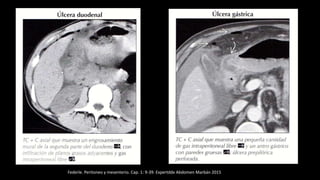

TC con contraste de paciente en la que se observa acumulación de aire por neumoperitoneo debido a

perforación de ulcus duodenal. Obsérvese la burbuja de aire que señala el punto de perforación.

E. Ballesteros Díaz, Patología mesentérica y peritoneal: desde la inflamación hasta la neo formación Seram2012/S-1242